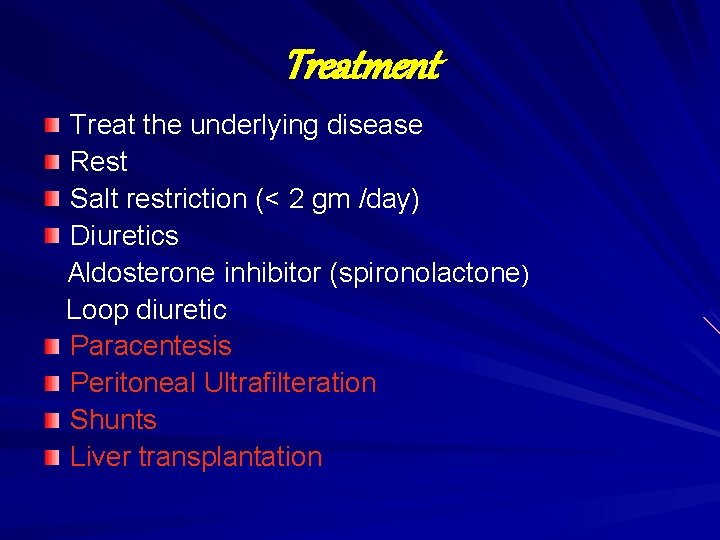

Treatment Treat the underlying disease Rest Salt restriction (< 2 gm /day) Diuretics Aldosterone inhibitor (spironolactone) Loop diuretic Paracentesis Peritoneal Ultrafilteration Shunts Liver transplantation